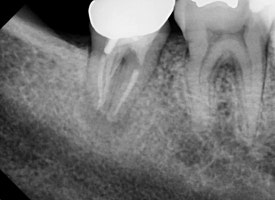

20250106

오른쪽 아래 어금니를 보겠습니다.

뿌리 끝을 감싸고 있는

검은 공간이 보이실겁니다.

치근단염증이라고도 합니다.

신경치료 후 염증이 재발되어

뿌리 끝에 매달려있는 것이지요.

치료 받으신지 오래되셨고,

예전의 치료가 아주 부족해보이진 않습니다.

뿌리 끝에

까만 염증 주머니가 달렸습니다.